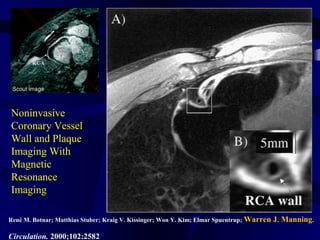

Noninvasive

Coronary Vessel

Wall and Plaque

Imaging With

Magnetic

Resonance

Imaging

René M. Botnar; Matthias Stuber; Kraig V. Kissinger; Won Y. Kim; Elmar Spuentrup; Warren J. Manning.

Circulation. 2000;102:2582